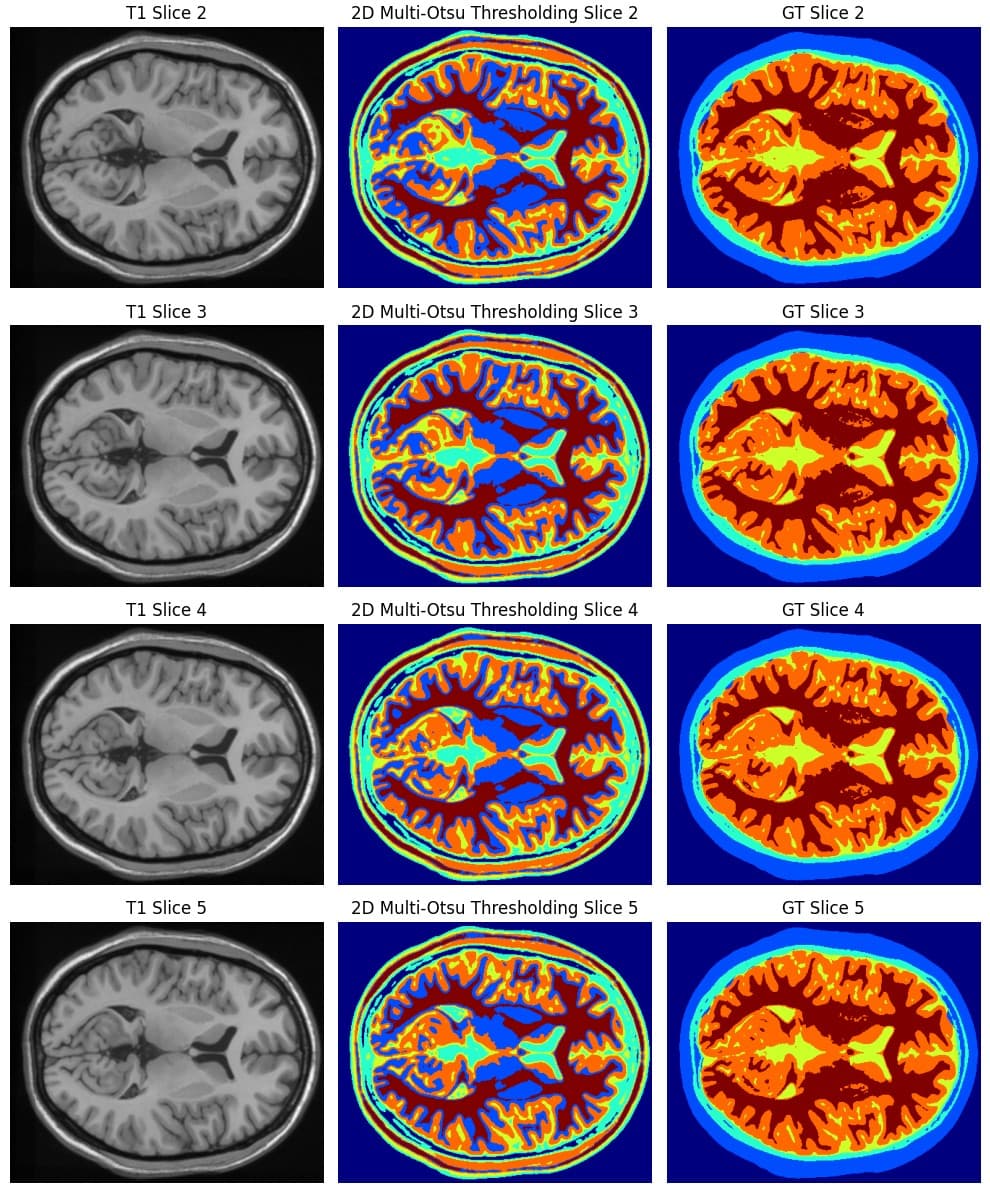

Brain MRI Tissue Segmentation

Developed a full pipeline for multi-class brain tissue segmentation on T1-weighted MRI volumes. Implemented unsupervised and classical vision techniques, including K-Means clustering, Multi-Otsu thresholding, and gradient-based Watershed segmentation. Evaluated performance on both 2D slices and full 3D volumes using Dice coefficient, IoU, precision, recall, and confusion-matrix analysis.